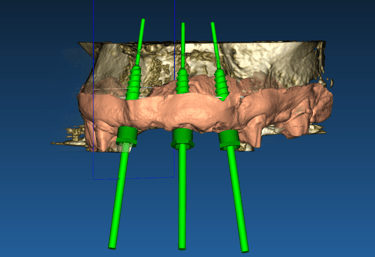

Cirugía guiada por ordenador

Colocar implantes nunca fue tan predecible

Planificación de casos

Situación inicial

Caso donde el paciente demanda estética en maxilar superior. Se retira el puente fijo y nos encontramos con dientes pilares que no pueden ser restaurados. Se indica exodoncia + implantes inmediatos.